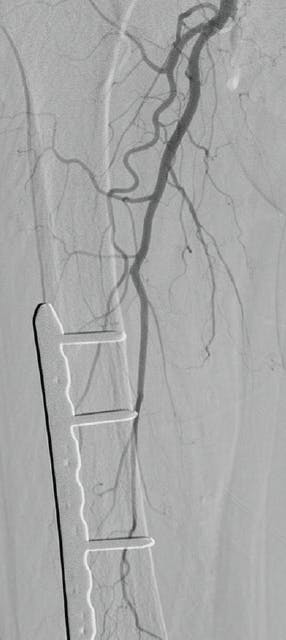

The surgeon did not feel as if there was a target for surgical revascularization and was not in favor of multilevel/multivessel open thrombectomy. It was decided to proceed with use of the Pounce™ Thrombectomy System, which allowed reestablishment of flow through the SFA and popliteal artery (Figure 2, Figure 3, and Figure 4). It also allowed us to place a catheter for thrombolysis focused on a tibial clot because the Pounce™ device is not indicated for the treatment of tibial arteries smaller than 3.5 mm.

Figure 2. Arteriogram of the right SFA after use of the Pounce™ Thrombectomy System.

Figure 3. Arteriogram of the right popliteal artery after use of the Pounce™ Thrombectomy System.